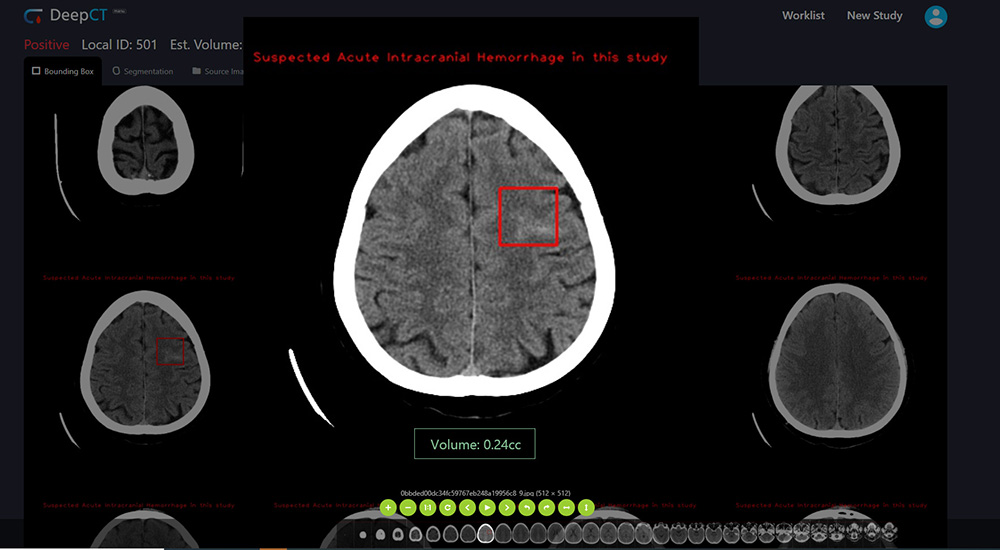

DeepCT volume

Deep01 Limited

Deep01 is the developer of DeepCT - world-leading AI-powered brain CT abnormalities detection and quantification system. It detects brain bleeds, fractures, midline shift, and calculates ICH Score automatically. Our AI makes doctors more efficiently in the medical process: For Neurosurgeons - help to evaluate patients For Emergency Physicians - help to triage patients For Radiologists - help to generate reports